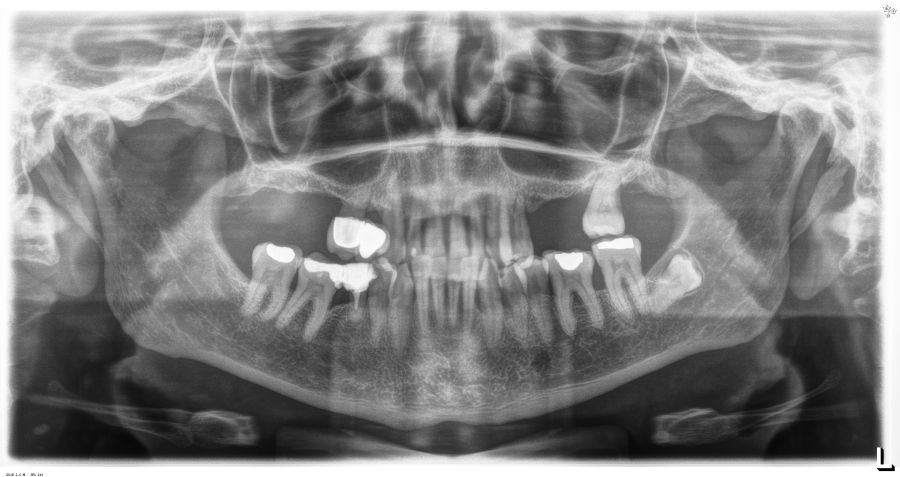

Presentamos el caso de una paciente femenina de 56 años de edad que acude a la consulta demandando un tratamiento con implantes dentales para reponer los dientes ausentes en ambos sectores posteriores maxilares. En ambos cuadrantes superiores, los molares se perdieron hace varios años. La paciente no se ha realizado la reposición de los mismos hasta ahora, ya que en otros centros consultados la propuesta terapéutica fue la de realizar injertos y regeneración ósea para poder ganar volumen óseo suficiente antes de colocar los implantes. La paciente busca otras alternativas menos invasivas y por ello acude a la visita. En las imágenes intraorales se observa la falta de los molares en los sectores posteriores maxilares con excepción del 27, que actualmente tiene un compromiso periodontal importante (Figuras 1-4). El resto de dientes también se encuentran afectados por una enfermedad periodontal avanzada con pérdida ósea horizontal (Figura 5).

Transcurridos 6 meses desde la carga inicial progresiva, se puede elaborar la prótesis definitiva, trasladando los parámetros de la prótesis provisional (Figura 27). La paciente continúa en seguimiento durante un año, realizándose radiografías de control para el monitoreo del hueso crestal, sin encontrarse pérdida ósea asociada en ninguno de los implantes (Figuras 28-29).